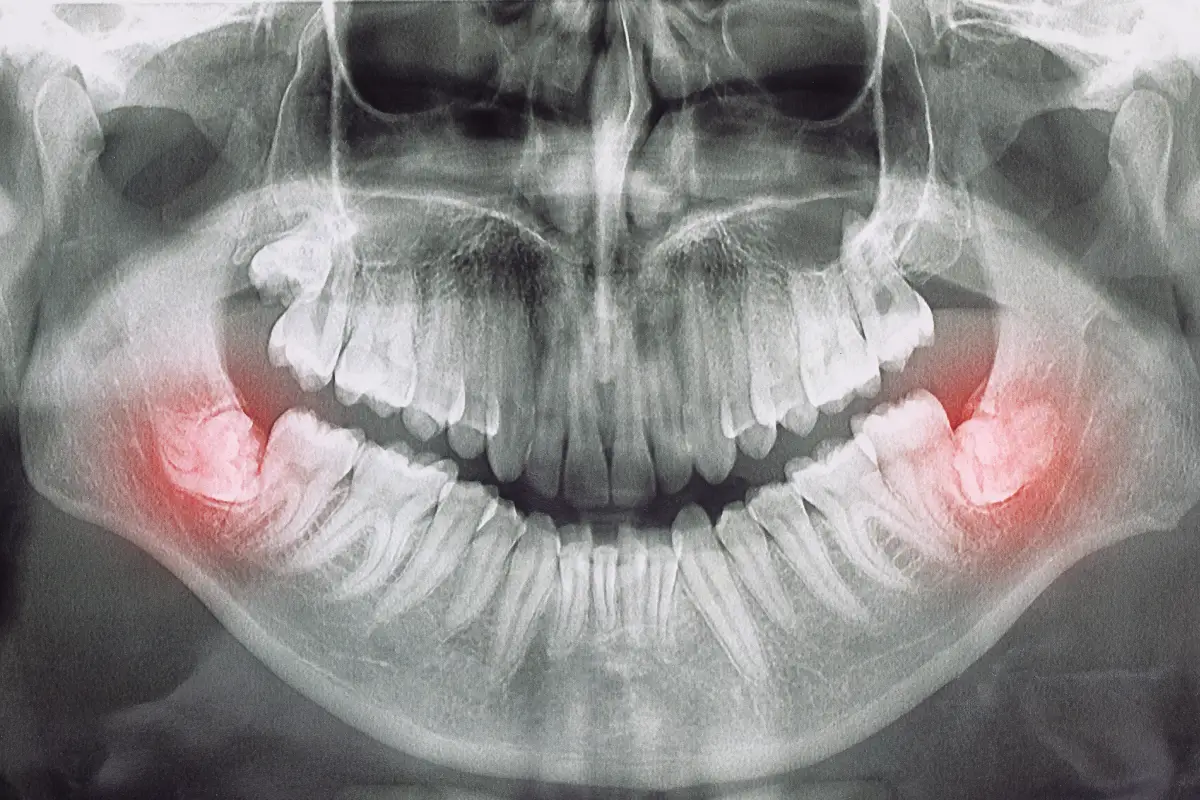

Wisdom Teeth Removal Recovery: Your Complete Guide to Healing Faster

Did you know that the first 72 hours after your wisdom teeth removal can make or break your entire recovery?